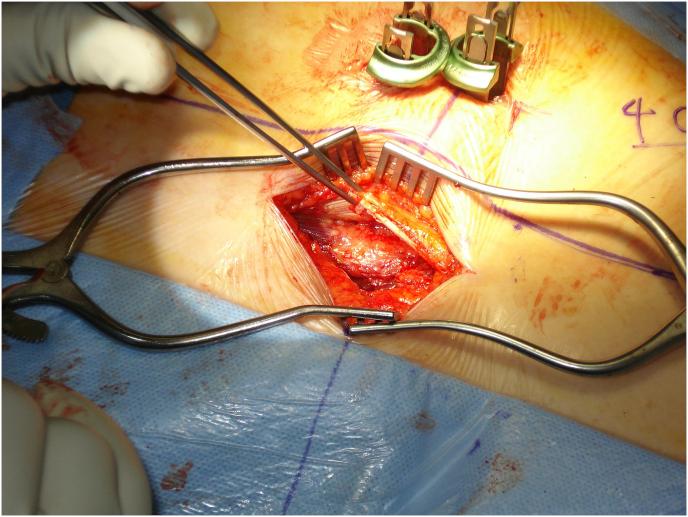

The purpose of this new approach is to develop a method that is less invasive as well as less traumatic and can provide a better exposure/view of the surgical field. Postoperatively, the patient has less pain, short hospital stay and less use of the postoperative pain control medications. As compared to other minimally invasive spine surgeries this approach results in less soft tissue damage, minimal muscle destruction, less retraction and better surgical outcome.

Approach is applicable for severe spinal stenosis as compared to other Minimally Invasive Spine Surgery (MISS) techniques that are only applicable for the mild to moderate stenosis or degenerative processes. This plane is avascular plane so no or less bleeding is anticipated from this procedure.

The technique facilitates bilateral canal enlargement through unilateral approach and provides accessibility to the contralateral foramen for decompression with perfect exposure and allows instrumentation through the lateral window with no muscle destruction.